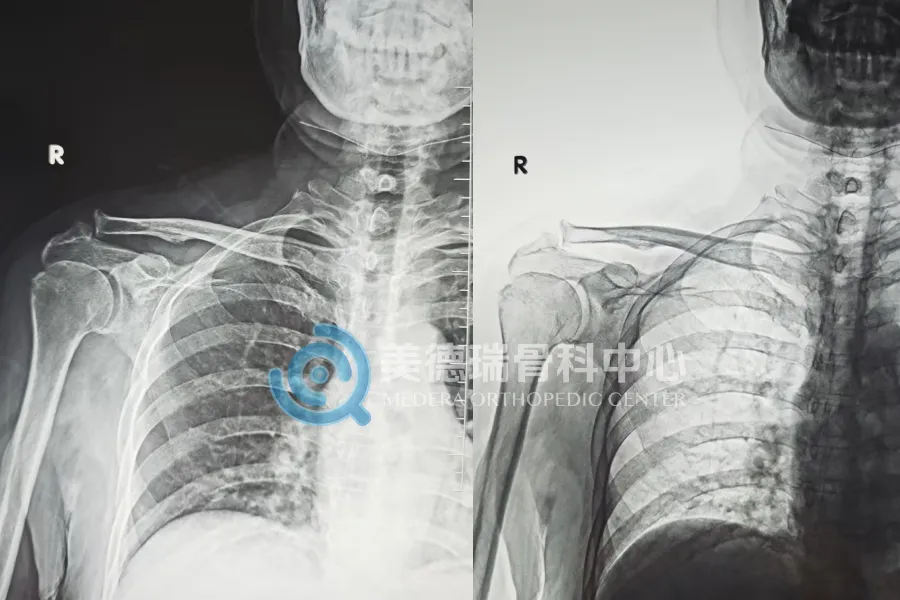

最近,平庄矿区医疗集团总医院美德瑞骨科中心在常态化开展肩关节镜治疗的基础上,又连续完成两例此类手术:右肩肩峰成形术 + 肩袖修补缝合术。手术由中心北京长驻专家团队协作完成。两位患者术后疼痛均明显减轻,肩关节活动度在康复训练中逐步改善,目前恢复进展平稳。

第一位患者属于门诊里常见的一类:右肩疼,活动受限,影像提示肩袖损伤合并肩峰撞击。这类问题最大的坑,是“凑合着用”。能忍就忍、能贴就贴、能理疗就理疗,短期能缓一缓,但不少人会越拖越不敢用那只手,力量下去、活动范围更小,最后还是得面对治疗选择。

第二位患者更麻烦:确诊为巨大肩袖撕裂。撕裂范围大、组织状态更差,修补时对关节镜下的操作精细度要求更高,处理不好,后面的功能恢复就容易受影响。